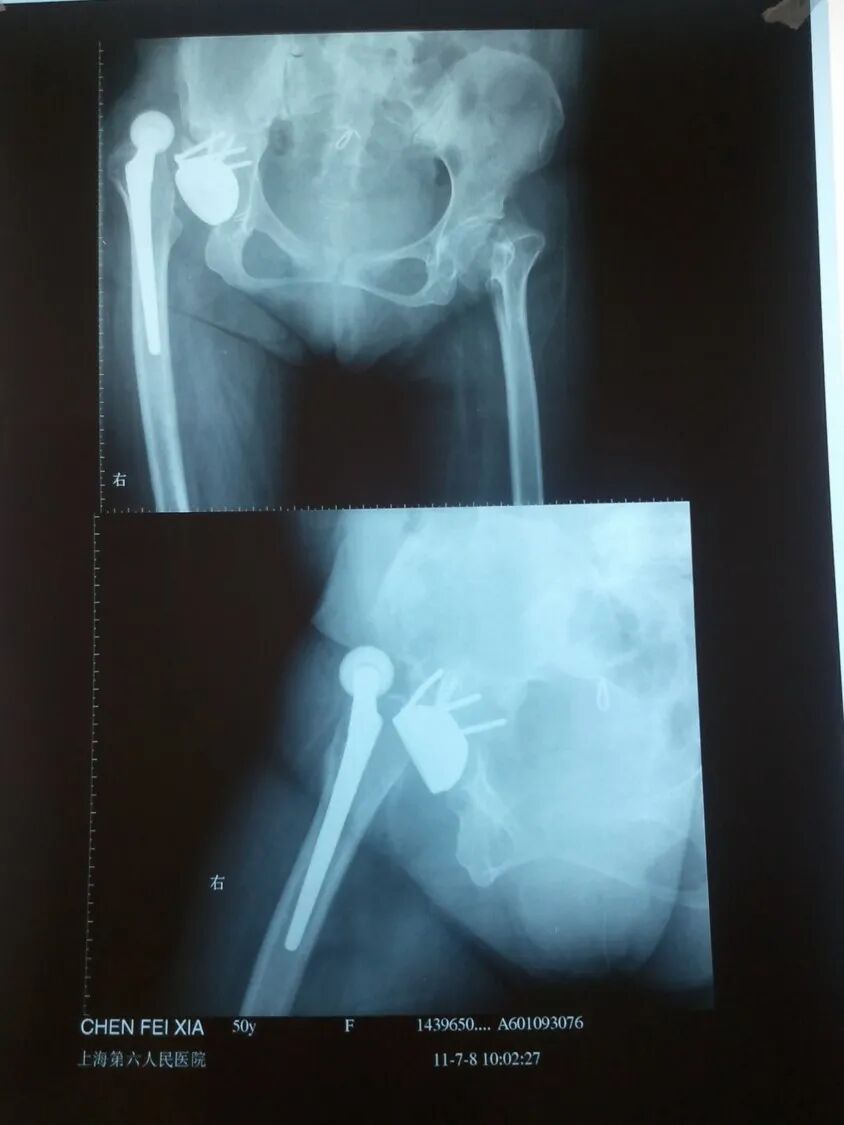

切开复位

术后4月,再一次脱位